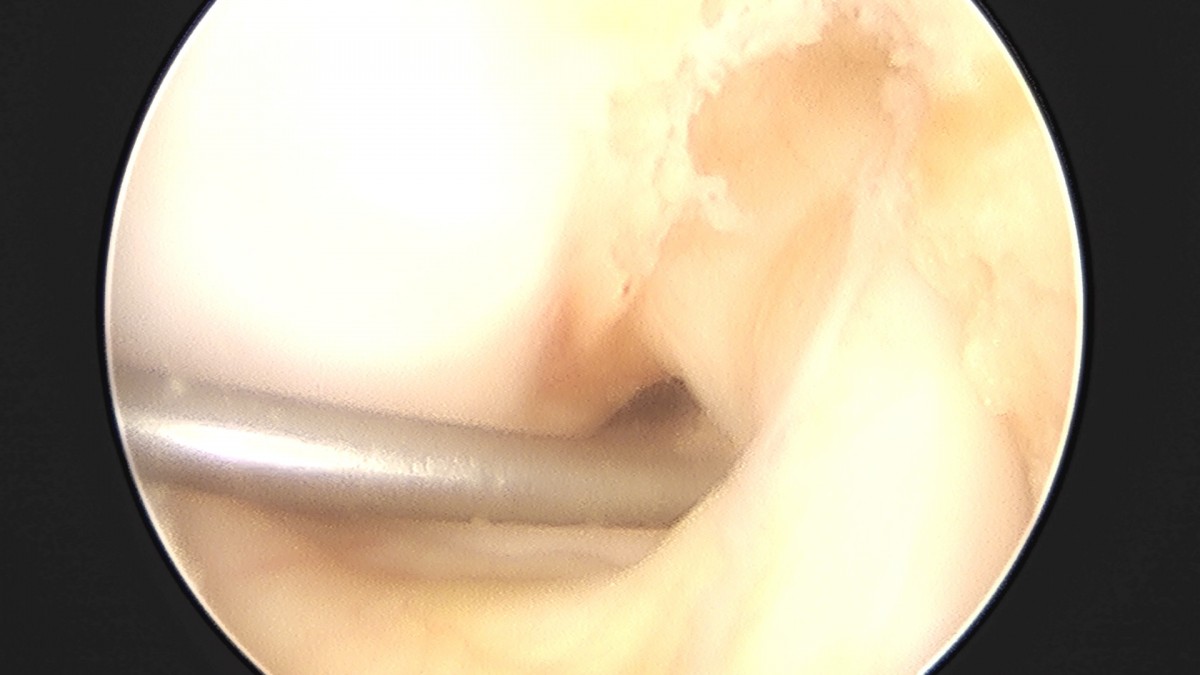

이재상원장님 무릎 반월상 연골판 절제술 윤여O 환자

dae765e4d9ac96aee867c9d6292d8784_1758004938_9333.jpg

dae765e4d9ac96aee867c9d6292d8784_1758004939_5152.jpg

dae765e4d9ac96aee867c9d6292d8784_1758004940_1088.jpg

dae765e4d9ac96aee867c9d6292d8784_1758004940_7066.jpg

dae765e4d9ac96aee867c9d6292d8784_1758004941_2738.jpg

dae765e4d9ac96aee867c9d6292d8784_1758004941_887.jpg

dae765e4d9ac96aee867c9d6292d8784_1758004942_4629.jpg

dae765e4d9ac96aee867c9d6292d8784_1758004943_0434.jpg

dae765e4d9ac96aee867c9d6292d8784_1758004943_6216.jpg

dae765e4d9ac96aee867c9d6292d8784_1758004944_1856.jpg